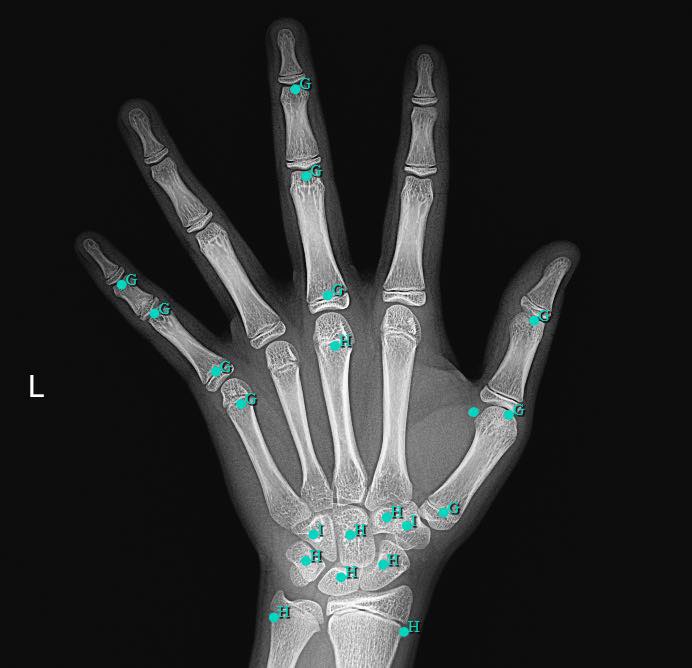

3、什么是骨龄,为什么要定期监测孩子骨龄?

骨龄是骨骼发育年龄的简称,在很大程度上代表了儿童真正发育水平,因此用骨龄来判定人体成熟度比实际年龄更为准确。

定期监测骨龄能知道孩子的生长潜力。孩子骨龄比实际年龄大,有早发育、骨骺线提前闭合的风险;孩子骨龄比实际年龄小,存在生长缓慢、滞后发育风险。